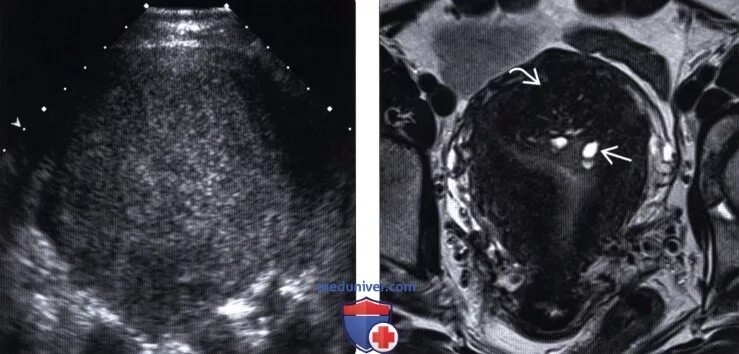

Диффузного аденомиоза миома матки